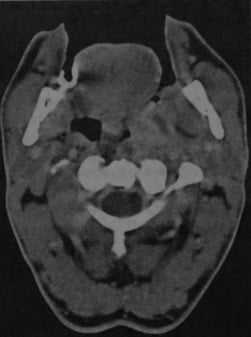

Абсцесс дна полости рта, расположенный справа около средней линии. КТ с контрастированием: объемное образование с типичным снижением плотности в центре, окруженное усиленной стенкой. Мелкий абсцесс слева, примыкающий к нервно- сосудистому пучку, с сопутствующим отеком поднижнечелюстных мягких тканей.